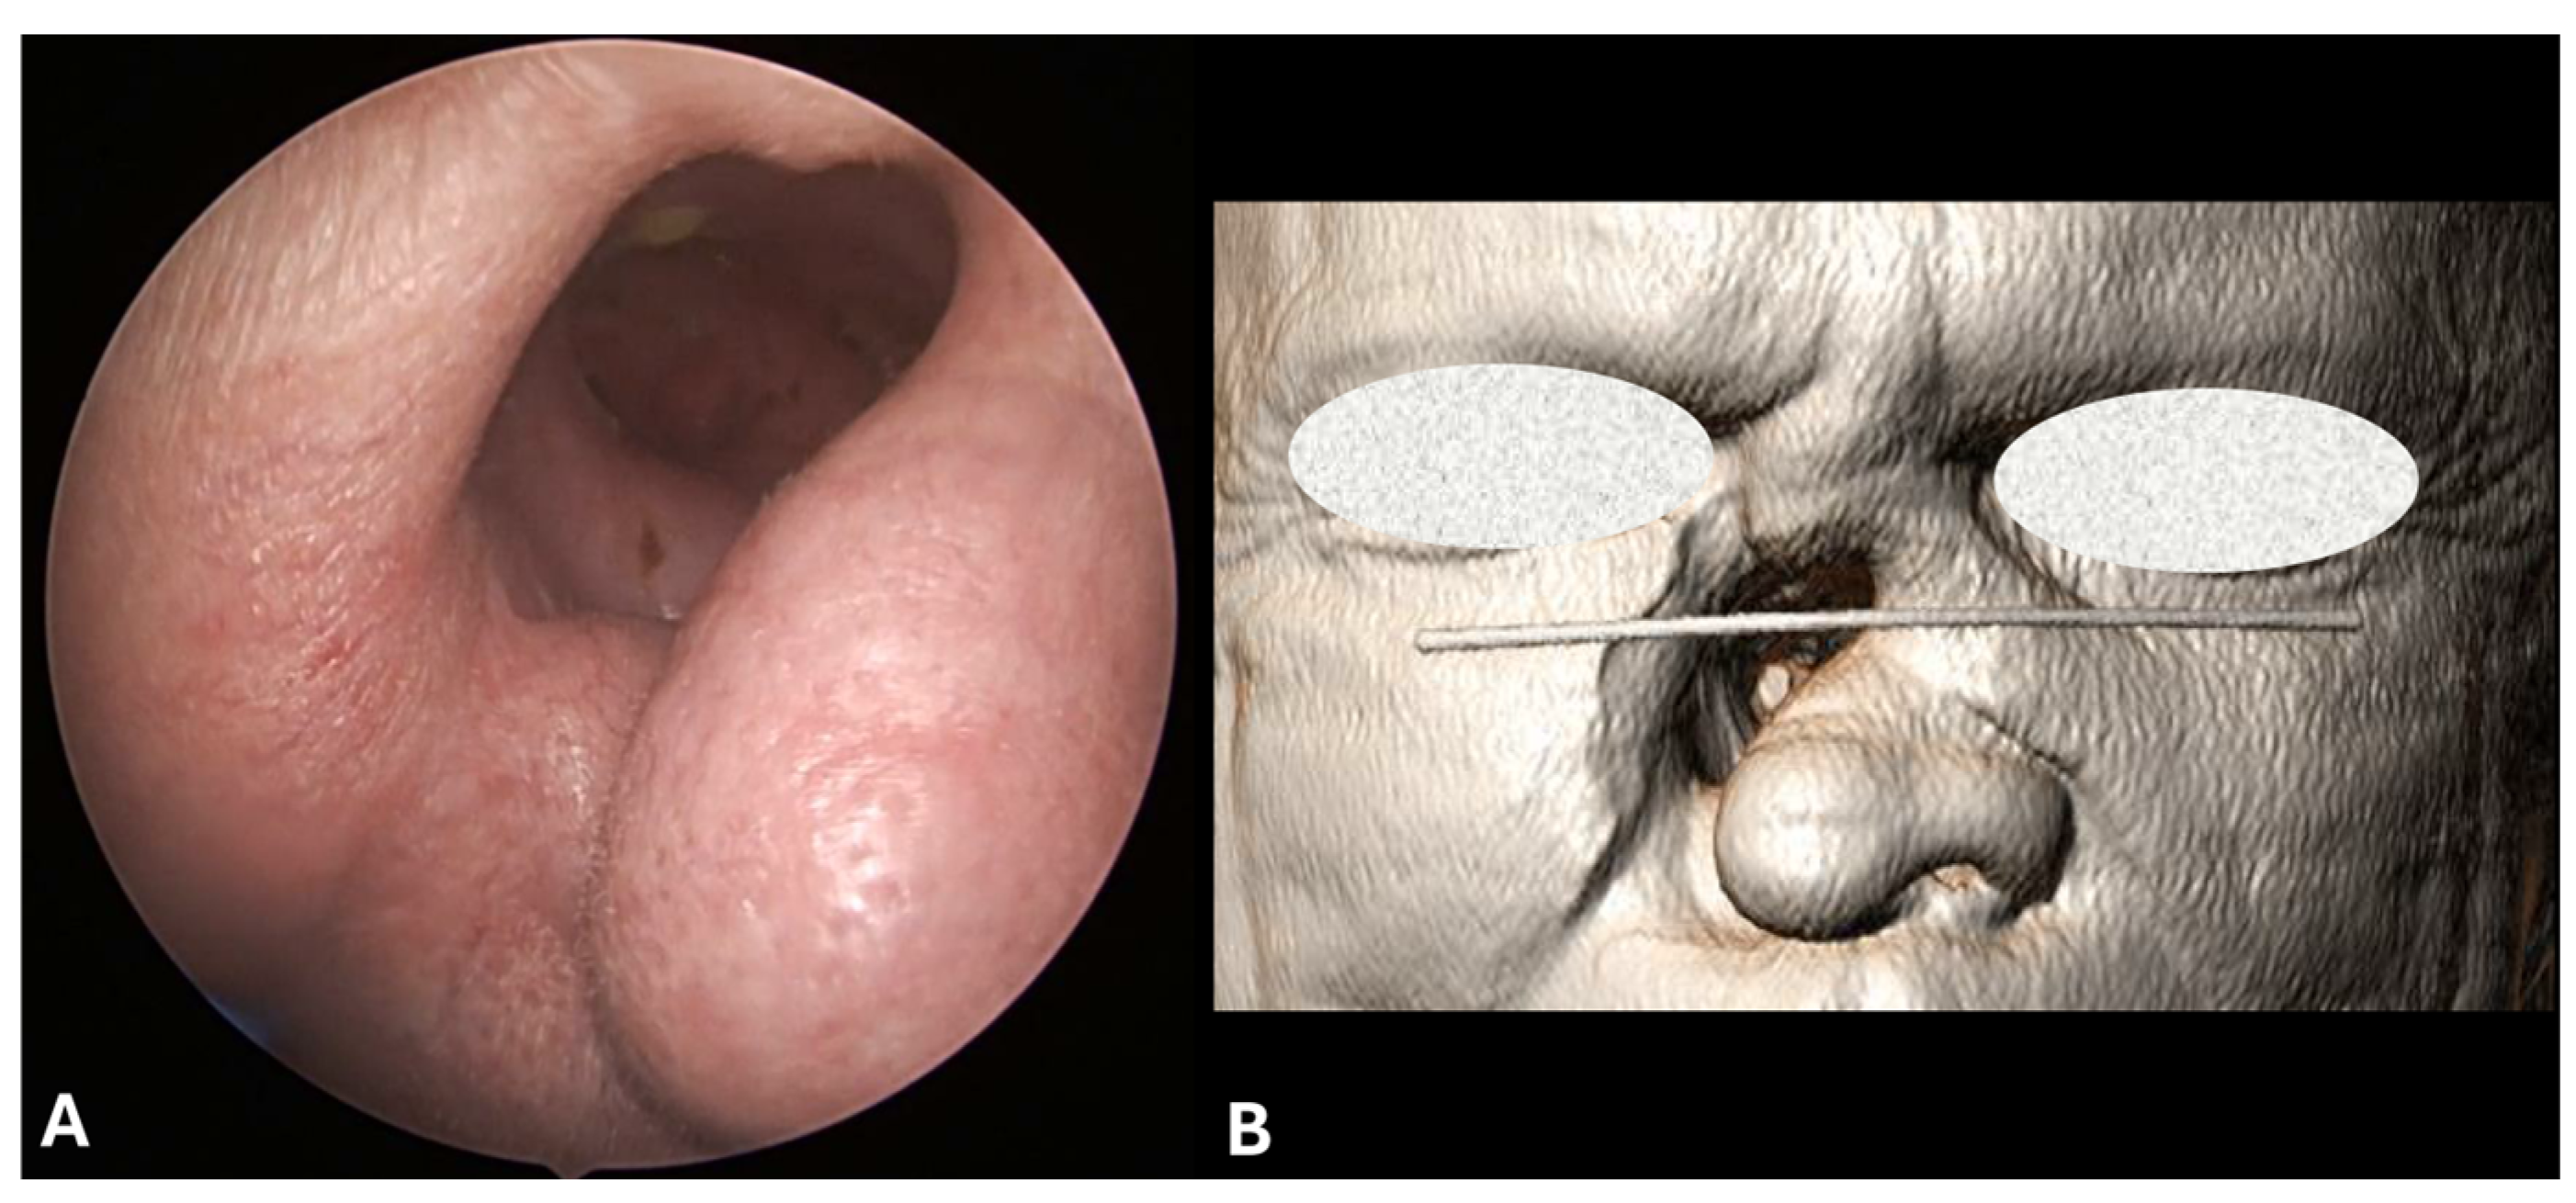

3.1.1. Clinical Features

3.1.4. Imaging